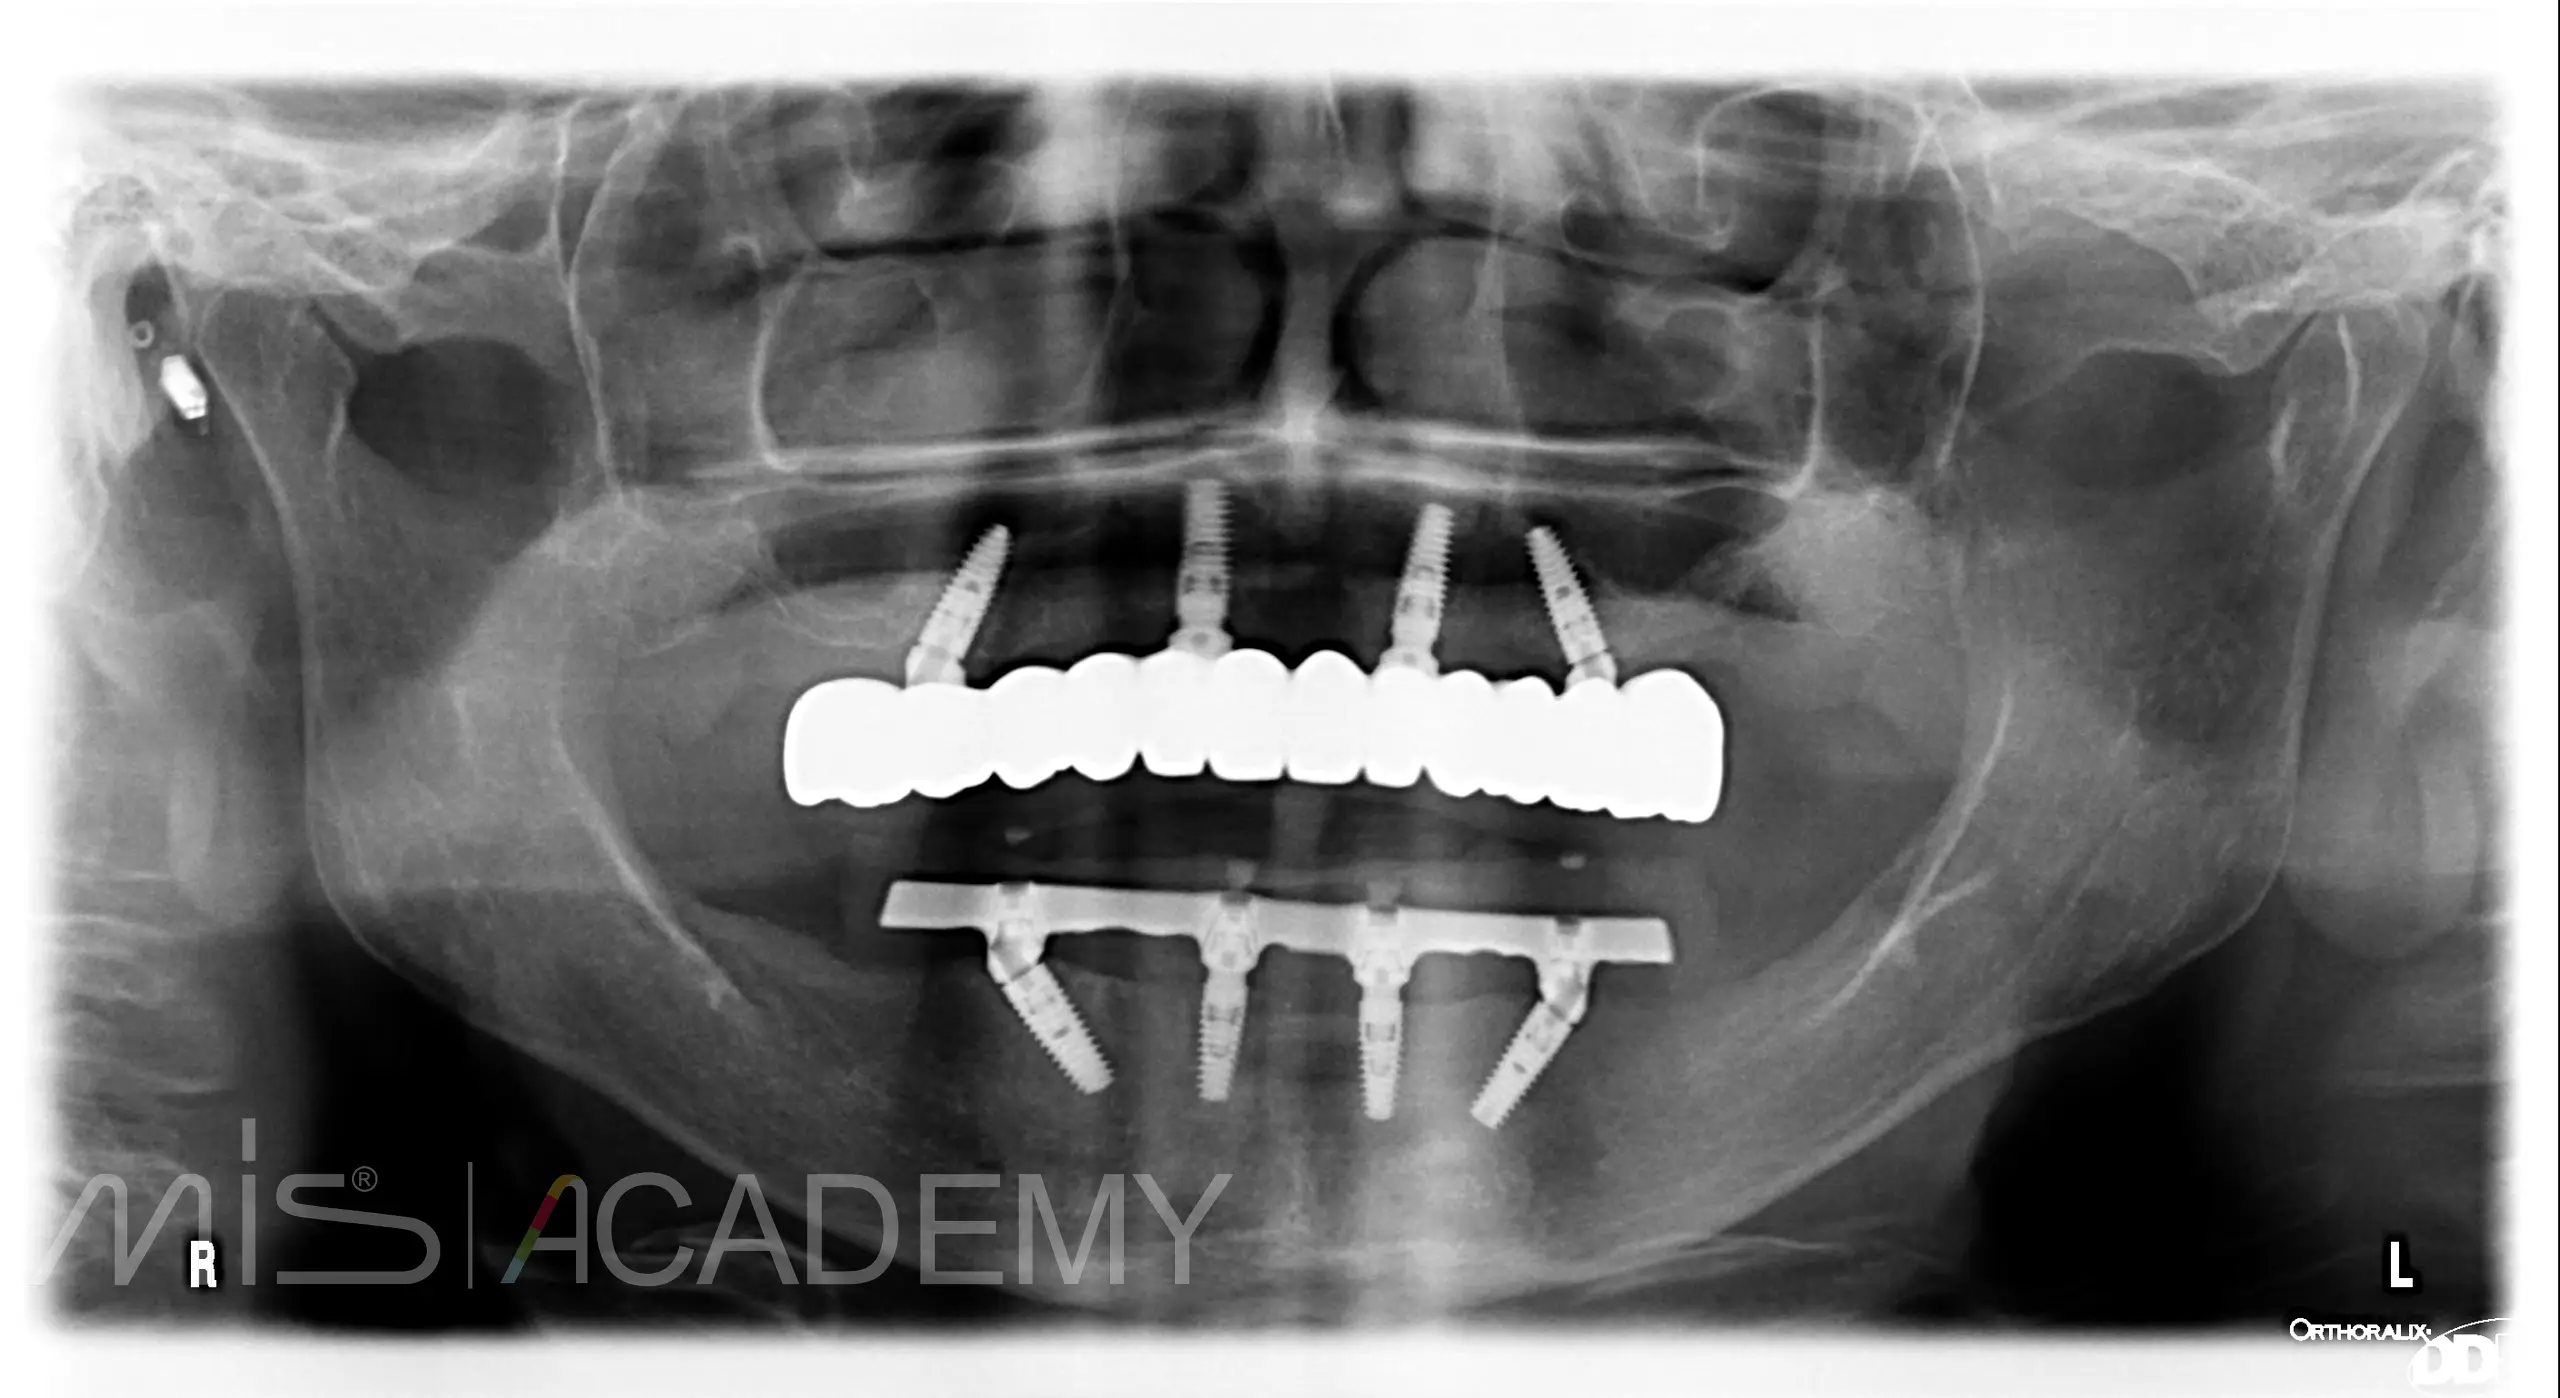

Установили по 4 имплантата на верхней и нижней челюсти и провели немедленную нагрузку металлопластмассовыми конструкциями.

После интеграции изготовили постоянные конструкции на верхней челюсти FP1 из диоксида циркония на титановой балке, на нижней челюсти FP3 из металлокомпозита.